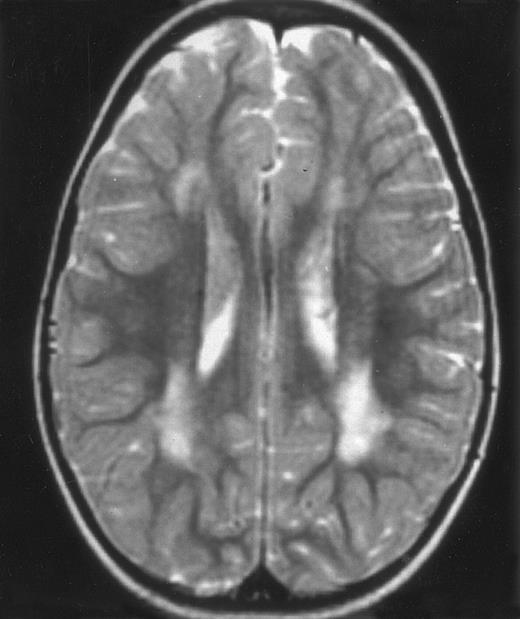

Three different aspects of brain imaging in HLH patients. (A) CT scan of a 3-month-old baby showing a large subdural effusion, several necrotic areas and hypodensities of the white matter. (B) Brain magnetic resonance of a 14-month-old boy showing large confluent areas of hypersignal in T2-weighted images. (C) Large symmetrical necrotic areas of cerebellar white matter in a 41/2-year-old girl (MRI).

Among the nine children with initial neurological symptoms, seizures were the most frequent initial symptom in the youngest patients, whereas ataxia was found in the two oldest patients (46 and 58 months old, respectively) (Table 1). All nine patients had the same CSF abnormalities as patients with meningitis only. Eight of these nine patients had a neuroradiological study performed at the time of their first neurological symptoms (Table 1). The two most frequent lesions were focal necrosis with parenchymal volume loss and atrophy (Fig 2A and C) and white matter abnormalities (Fig 2B). Several small focal lesions with hypersignal at MR imaging that enhanced after administration of gadopentate dimeglumine (or contrast on CT scan) were also observed in two cases.

Abnormalities on brain imaging appeared to roughly parallel the severity of clinical manifestations. All patients with neurological symptoms, but also half of the patients with initial meningitis, had abnormal brain imaging usually consisting of a combination of diffuse white matter abnormalities and necrotic areas with parenchymal volume loss, as previously described.8,23 In patients with isolated meningitis, however, only white matter abnormalities were detected, whereas necrotic lesions and cerebral atrophy were found in patients with neurological symptoms. These lesions progressed despite chemotherapy. Previous neuropathological studies have demonstrated infiltration by monocytes and activated lymphocytes of leptomeninges and brain parenchyma along penetrating vessels.24,25 Infiltration is associated with focal and confluent areas of myelin pallor, as well as neuronal loss, tissue necrosis, and cavitation,24,25 findings that were also demonstrated in the neuropathologic study of five patients in our series. Leukocytes infiltrating the CNS probably secrete cytokines and other neurotoxic factors, such as tumor necrosis factor-α (TNF-α), which may be responsible for the myelinic alteration observed in neurologically asymptomatic patients. Infiltrating leukocytes could also activate in parallel the numerous resident brain macrophages (the microglial cells) and astrocytes, which in turn, can secrete neurotoxic glutamate and free radicals.26